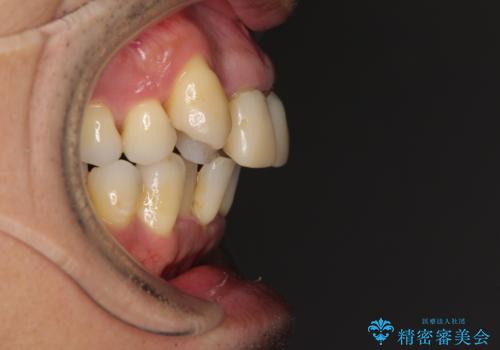

八重歯と突出感を改善 ワイヤー装置での矯正治療

- 八重歯を気にして来院された患者様です。

上顎前歯の突出感と右上の八重歯を気にされていたので、上顎左右の第一小臼歯2本を抜歯し、ワイヤー装置にて矯正治療を行うこととしました。

食いしばりにより奥歯がすり減っており、咬み合わせが定まるまで時間がかかりましたが、整った口もに仕上がりました。